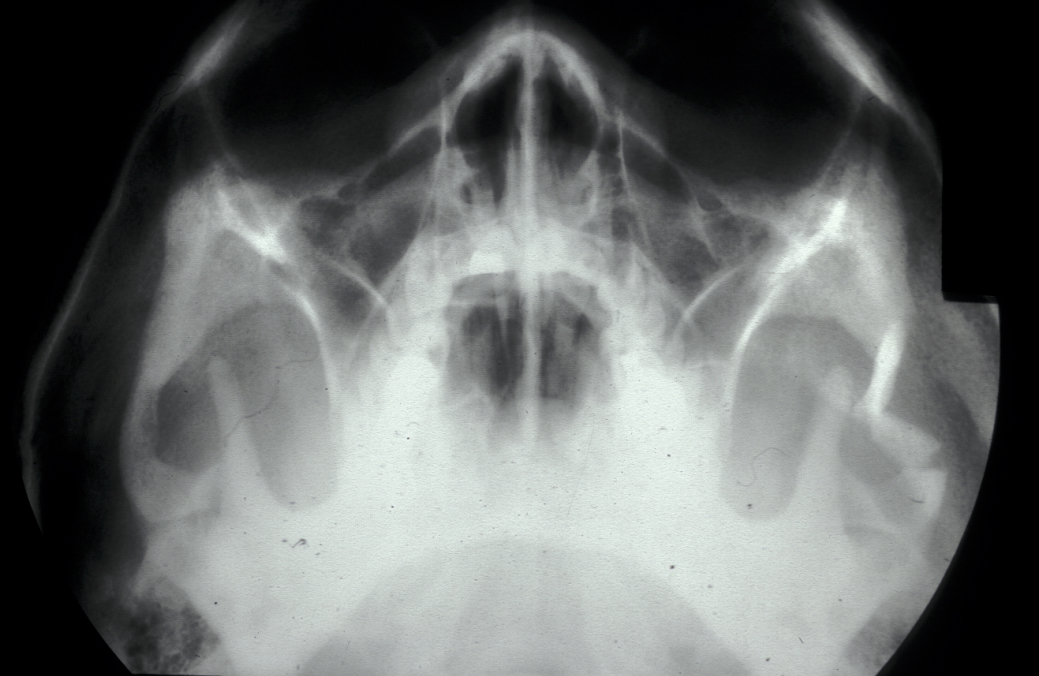

Isolated zygomatic arch fractures are best visualised on a submentovertex view (view at base of skull). However, an adequate view of the fracture is usually visible on occipitomental views (see Figure 9).

Figure 9: Depressed fracture of the zygomatic arch causing trismus.